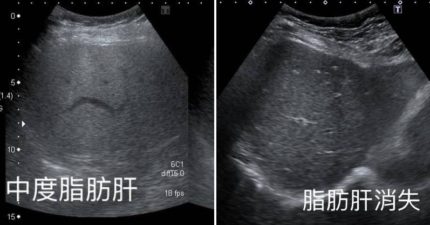

她「少吃1物」中度脂肪肝消失 醫追問驚:一年瘦了快10公斤

July 4, 2025

台灣, 知識